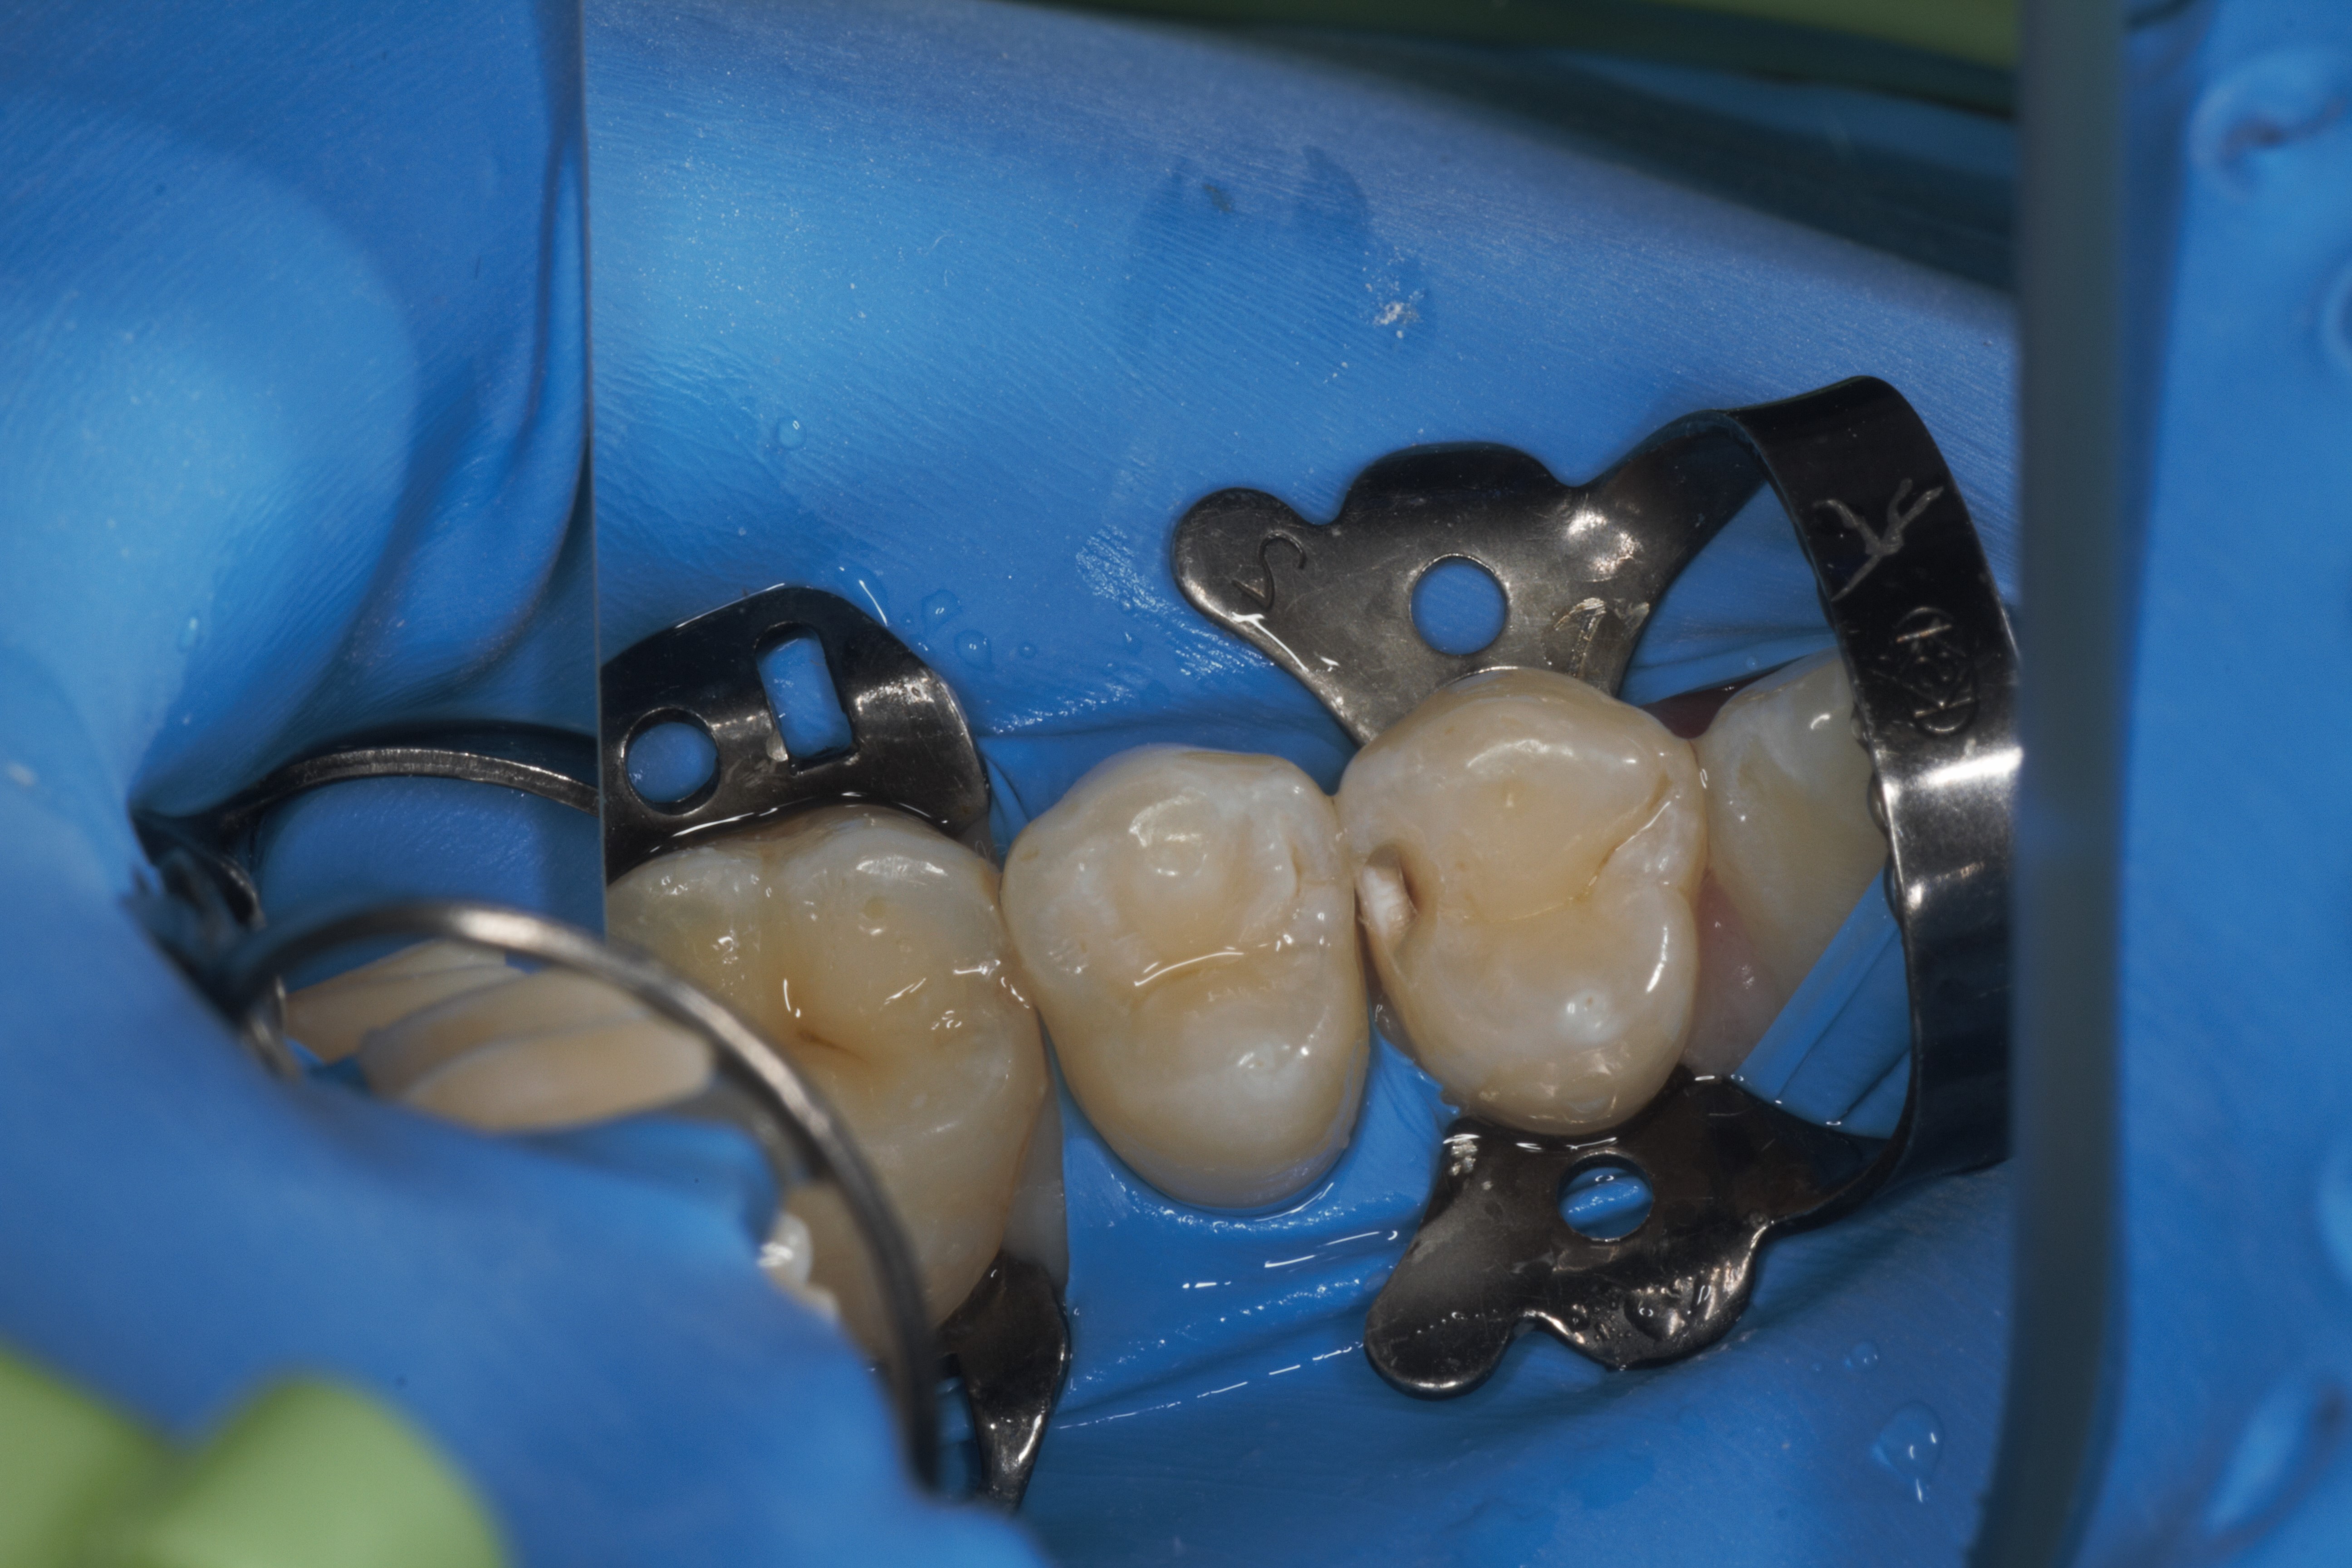

- Эстетическая реставрации жевательной и фронтальной группы зубов современными пломбировочными материалами, диагностика кариеса на ранних этапах развития, предупреждение образования вторичного кариеса в области запломбированных зубов

- Владение современными методиками пломбирования корневых каналов, обработки и распломбировки многокорневых зубов любой степени сложности